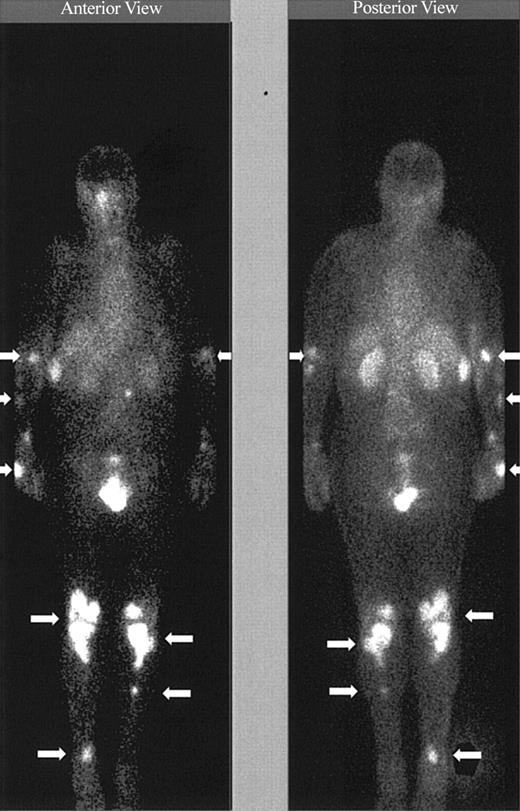

Imaging with Indium. Images obtained 20 minutes and 3 hours after infusion of the 111In-labeled DOTA-biotin demonstrated a rapid clearance of the blood pool radioactivity with early prominent kidney and bladder imaging reflecting the urinary route of excretion (Figure 3). Tumor sites were well delineated by 3 hours in all patients and were often visualized as early as 20 minutes after injection (Figure 3). Figure 4 demonstrates dramatic radiolocalization of the radionuclide in known nodal and extranodal tumor sites: subcutaneous nodules, skin, testes, and knees. The patient had serious knee pain, and magnetic resonance imaging confirmed that the unusual involvement around the knee area was consistent with non-Hodgkin lymphoma involvement of bone. Tumor localization of radioactivity persisted for the duration of the study. In 15 tumors evaluated, the estimated localization per gram of tumor was 0.01% to 0.04% of the injected dose.

Tumor targeting of known sites of disease. Image obtained 46 hours after the administration of 111In (5 mCi)/90Y (15 mCi/m2)–DOTA-biotin. Gamma camera whole-body scans of patient no. 3 (anterior view on left and posterior view on right) obtained 46 hours after infusion of 111In/90Y-DOTA-biotin. Arrows are showing radionuclide localization to known sites of tumor involvement.